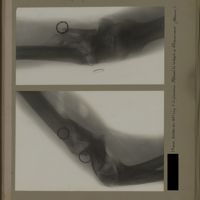

0139 - Page 27 - [Radiographies du coude]0139 - Page 27 - [Radiographies du coude]

0144 - Page 32 - [Radiographies du coude]0144 - Page 32 - [Radiographies du coude]

0153 - Page 41 - [Radiographies du coude]0153 - Page 41 - [Radiographies du coude]

0175 - Page 63 - [Radiographies du coude]0175 - Page 63 - [Radiographies du coude]

0201 - Page 89 - [Radiographies du coude]0201 - Page 89 - [Radiographies du coude]